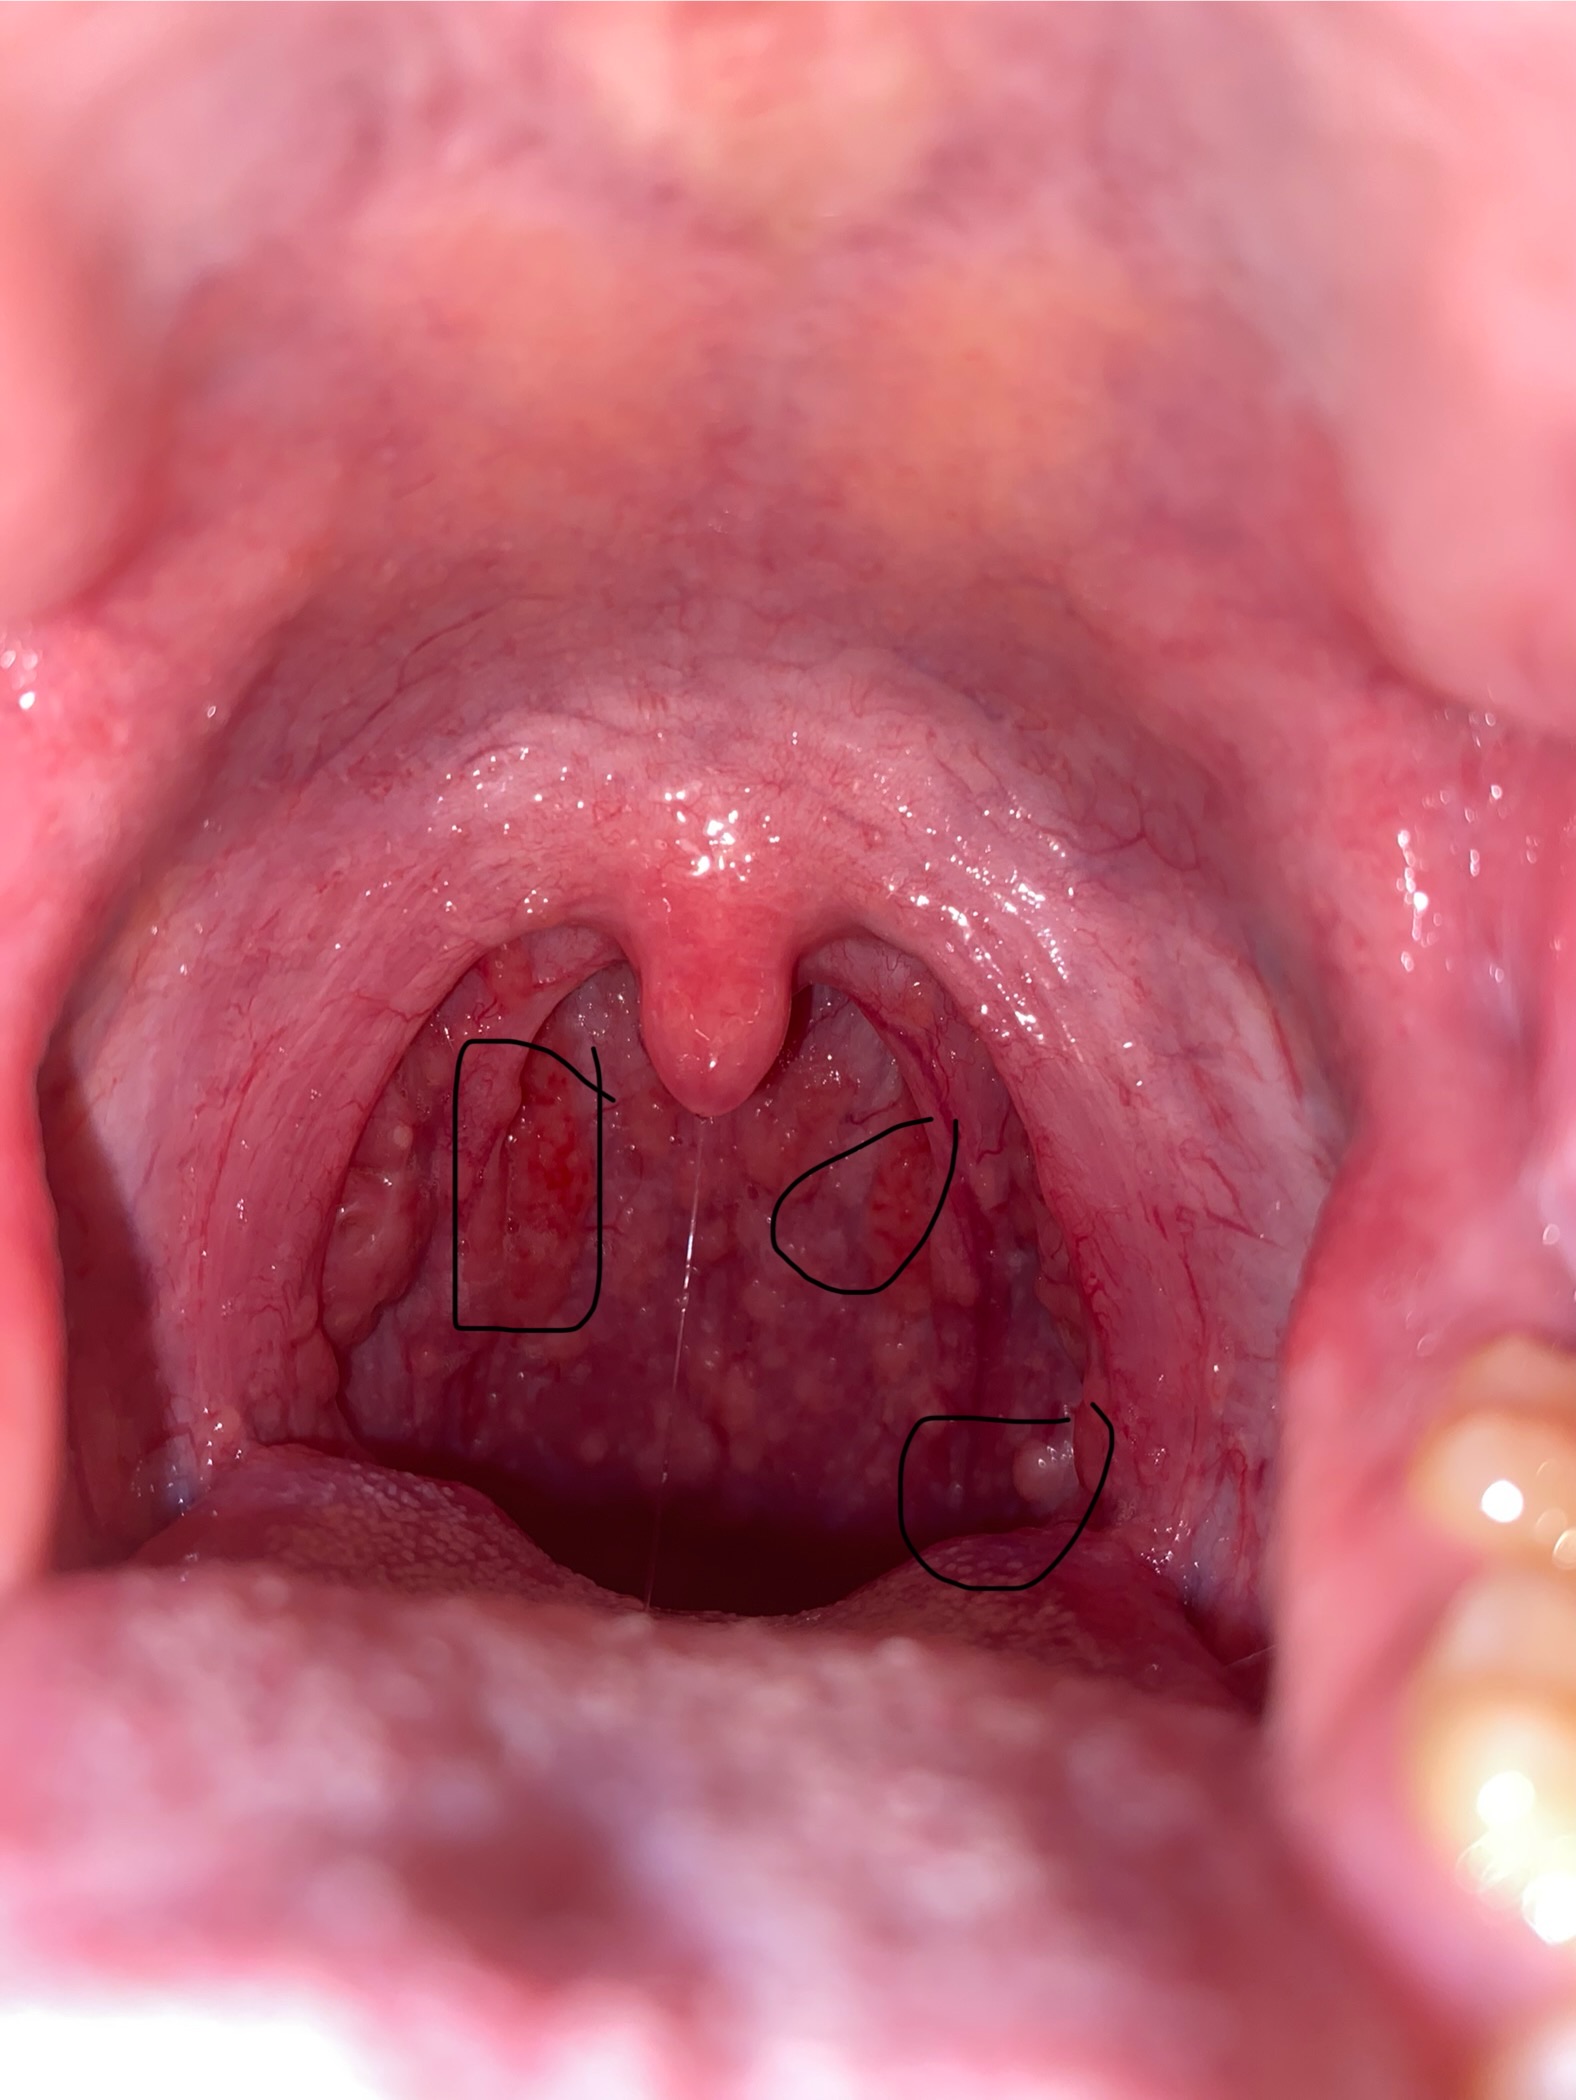

Cháu chào bác sĩ ạ cho cháu hỏi là họng cháu bị sưng và nổi hạt như này và thi thoảng bị ho thì là bị gì và có nguy hiểm không ạ ( cháu nổi hạt hơn tháng rồi ạ )